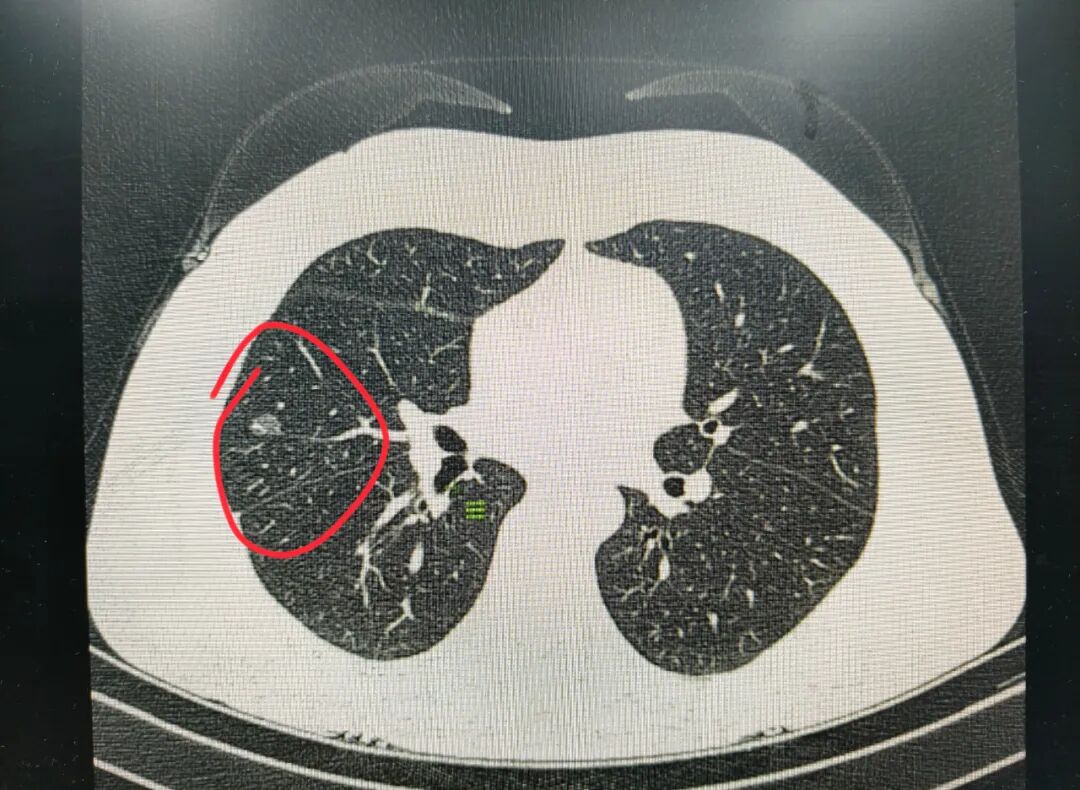

这位55岁的女性患者不曾想到 一次常规体检会给自己带来 一块沉重的“心头大石” 报告单上右肺中叶磨玻璃结节 这几个冷静的文字 让她和家人瞬间紧张起来 肺结节?虽然当时医生建议先观察 但这“不速之客”仍让她寝食难安 要不要切?怎么切? 传统手术想想就让人望而生畏 长长的疤痕、全身插满管子、漫长的恢复期 每一个念头都加重着这份焦虑 (右肺中叶外侧段)贴壁生长型肿瘤 10个月后,她带着沉重又忐忑的心情 到我院找到贺延法主任 经CT检查,发现她的结节已明显增大 胸外科团队经仔细评估 结合影像学特征,考虑早期肺癌可能 得知这位患者对术后疤痕的顾虑 贺主任团队详细讨论后 带来一套“美丽又安全”的手术方案 可以采用无管化手术技术(Tubeless) 经乳晕进行单孔胸腔镜手术 让手术切口实现“隐身” 这是肺结节治疗领域的微创美学突破 既满足了肿瘤根治的医疗需求 又兼顾了患者的美观诉求 无管化?隐形? 这些新鲜词一下子抓住了患者的心 经乳晕隐匿切口手术厉害在哪儿? 1.疤痕玩“隐身” 乳晕颜色深、还有皱褶,愈合后疤痕就跟穿了迷彩服一样,根本找不到!可较好缓解患者术后外观顾虑,减轻心理压力。 2.疼痛感大减 手术创伤更小,疼痛直接打对折! 3.住院像出差 两三天就能出院回家,住院体验从“漫长煎熬”变成“短暂出差”。 手术时,没有想象中的“大动干戈” 麻醉医生采用精准的监护麻醉 贺延法主任团队凭借精湛的技术 通过隐藏在乳晕的2.5厘米微小切口 如同通过一个“钥匙孔” 精准抵达“目标区域”——右肺中叶 顺利为患者行经乳晕无管单孔胸腔镜手术 术中无气管插管、中心静脉置管、 尿管以及胸腔引流管 全程保留自主呼吸 让该患者惊喜的是 术后,她就可以下床活动了 没有各种管路的牵绊 她感觉自己一点也不像 传统意义上的“大手术”病人 术后照片 “隐形”切口 近年来,我院胸外科手术技术 已实现多代跨越 如今隐匿微单孔(乳晕旁切口) 胸腔镜手术的顺利开展 更是将“微创”升级为“无痕” 正如贺延法主任所说 “我们不仅要治好患者的‘身病’, 更要关注他们的‘心病’。” 以最小代价助力患者“快速康复” 是我们一直在努力做的事